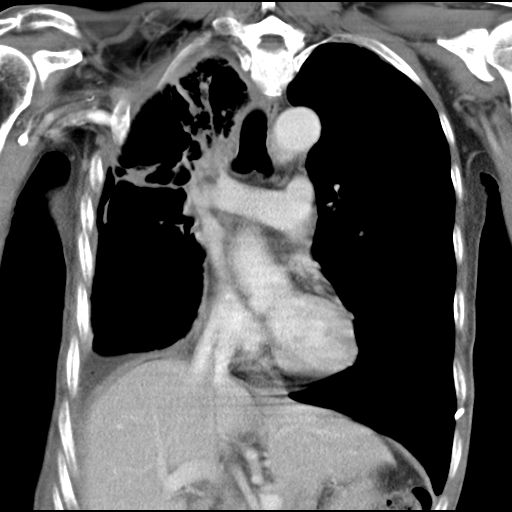

2020年5月12日,何叔來到復大就診,檢查結(jié)果:入院查CT示右肺中央型肺癌并右肺上葉及中葉阻塞性肺不張表現(xiàn),肺腺癌T3bN2M1 Ⅳ期,伴胸膜、縱膈、右肺門等多發(fā)淋巴結(jié)轉(zhuǎn)移,左側(cè)胸腔中大量積液,右側(cè)胸腔少量包裹性積液。針對何叔的病情,復大專家團隊立馬組織會診,先后給予何叔靜滴安維汀和兩次動脈DSA+灌注化療聯(lián)合PD-1治療,何叔的呼吸癥狀得到改善,腫瘤也從8.6公分縮小到4公分。

治療后